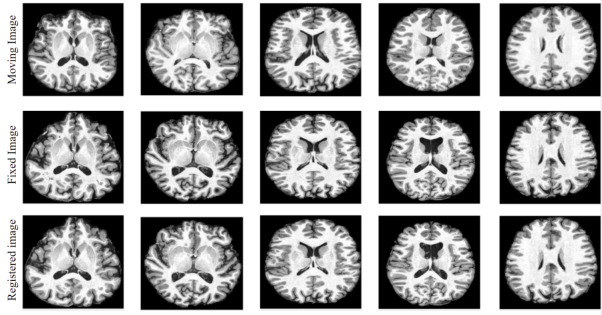

The proposed image registration algorithm was used to register MRIs of different individuals. The mean squared error (MSE) was used as a similarity metric along with cubic interpolation. To analyse the performance visually, ten 3T MRI scans were collected. Five images collected from 20-30 year old male subjects were considered as moving images and five images collected from 40-50 year old female subjects were considered as fixed images. Performing a good registration is challenging with this selection of moving and fixed images. The high resolution MRI scans used for this experiment are openly available at http://dx.doi.org/10.17632/gnhg9n76nn.1. The registration results for these five different pairs are shown in Fig.5 where only a sample slice is visualized for the 5 cases. The quality of registration can be assessed by observing the degree of match between images in the last two rows of each column. The results indicate that the proposed method is good at capturing complex inter-subject deformations.

Refer to caption

Figure 5: Inter-subject image registration for 5 pairs of volumes (in 5 columns). Only sample slices are shown.